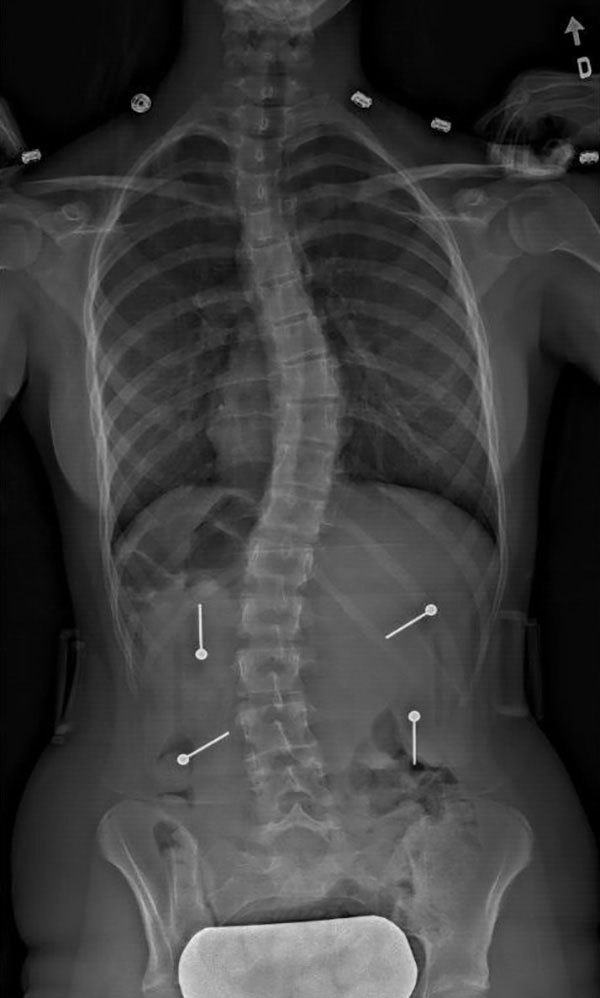

Scoliose double – comporte deux courbes, l’une située au niveau thoracique et l’autre soit en thoraco-lombaire ou en lombaire

![]() |

* Les photos ci-haut sont tirées de Different scoliosis patterns radiological and clinical highresolution.jpg par Weiss HR, Goodall D [CC BY 2.0 (http://creativecommons.org/licenses/by/2.0)], via Wikimedia Commons